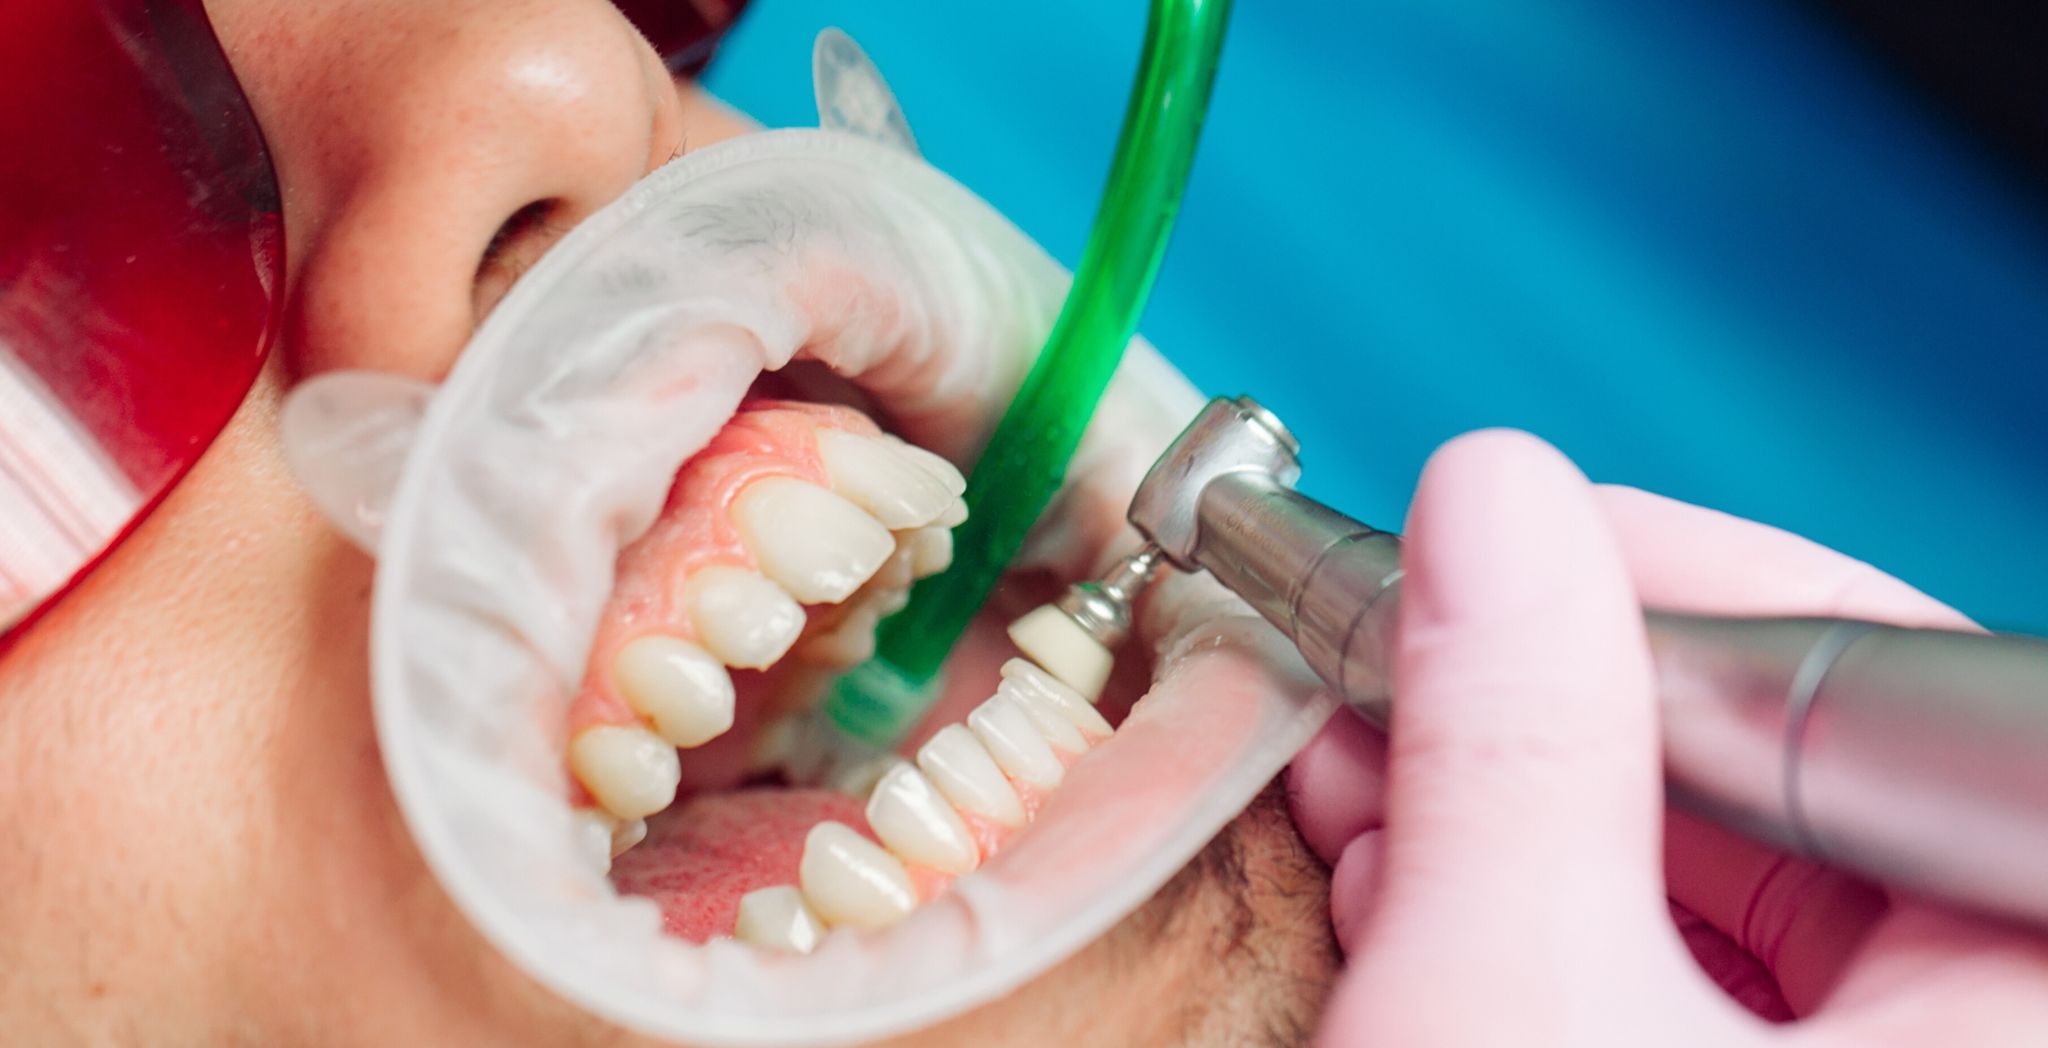

Professional teeth cleaning, medically referred to as "supragingival scaling" , is the process of using specialized instruments to remove supragingival calculus (tartar), plaque, and stains from the teeth . Unlike daily brushing, professional cleaning can access and thoroughly clean areas that toothbrushes cannot effectively reach, such as the gumline and deep between the teeth, effectively removing established calculus and tenacious plaque deposits .